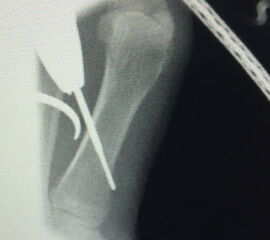

Zusätzlich schränken Wachstumsfugen die Wahl der Osteosynthese ein. Eine die Fuge kreuzende Osteosynthese ist ausschließlich mit Kirschner-Drähten möglich (Abb. 3).

Abb. 3 a-j: Beispiel einer Calcaneusverschiebeosteotomie mit offenen Wachstumsfugen und der entsprechenden Osteosynthese mit Kirschner Drähten. Lokalisation der Osteotomie (a), Lage der Fräse (b-d), Drahtlage mehrere Ansichten (e-h), Heilung der Osteotomie 4 Wochen postoperativ und Entfernung der Drähte (i-j).